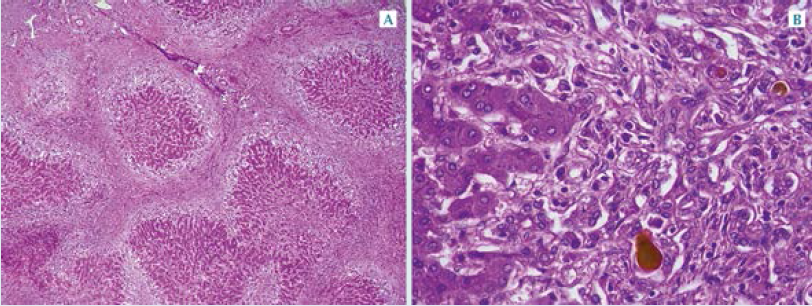

Se realizó la autopsia completa. De manera externa mostraba ictericia intensa, afectación de la piel y todas las mucosas. El hígado estaba aumentado de peso y tamaño (480 vs 350 g), tenía tinte verdoso, nodularidad difusa y consistencia aumentada. No tenía la vesícula biliar; las vías

biliares extrahepáticas se palparon de consistencia fibrosa y en los cortes seriados no se evidenció luz permeable. El bazo también estaba aumentado de tamaño y peso (150 vs 35 g). Figura 3

Los cortes histológicos adyacentes al páncreas mostraron el conducto colédoco (conducto biliar común) con obliteración parcial de la luz, debido a estenosis fibrosante. El conducto

hepático común solo mostró un cordón fibroso sin remanentes de la vía biliar. Figura 4

Los cortes del parénquima hepático exhibían tabiques fibrosos que disecaban y rodeaban nódulos redondeados e irregulares de hepatocitos, que a diferencia de otras formas de cirrosis éstas son características de la cirrosis biliar. Los islotes parenquimatosos estaban deglutidos por más tejido fibroso y edema; no obstante, en la biopsia las bandas de tejido fibroso fueron más amplias y el hígado tenía estructura mixta micro y macronodular. Figura 5